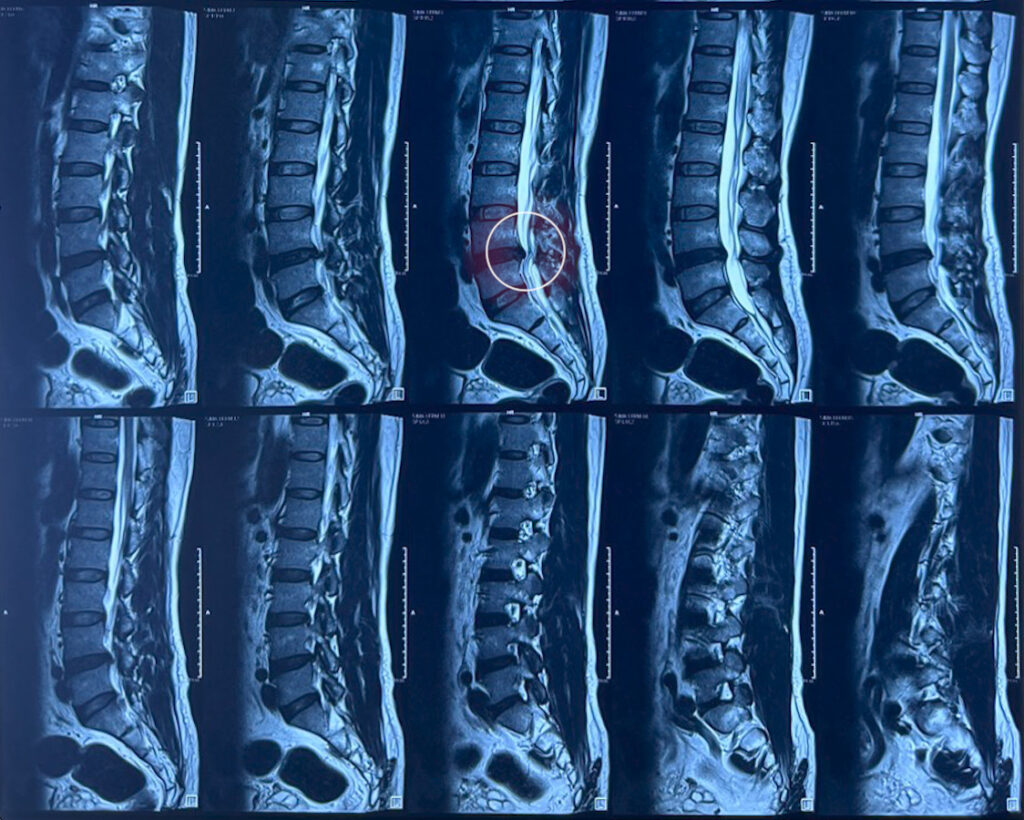

- Chụp X-quang: Chụp X-quang cột sống giúp xác định vùng xương bị tổn thương hoặc phát hiện những tổn thương của vùng đĩa đệm hay các bệnh lý nhiễm trùng.

- Chụp CT hoặc chụp MRI: Hình thức này giúp thấy rõ những hình ảnh chi tiết của các vị trí xương và xem xét được vùng tổn thương.

- Chụp tủy đồ: Biện pháp này giúp xác định nguyên nhân đau có phải từ đĩa đệm hoặc đốt sống hay không.